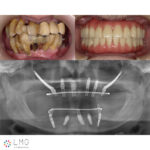

下顎オールオンフォー、上顎ザイゴマインプラント

「ザイゴマインプラント治療」を行われた患者さまのビフォーアフターをご紹介します。

手術後口腔内

手術後パノラマX線写真

日帰り全身麻酔により、上下顎同時に手術。